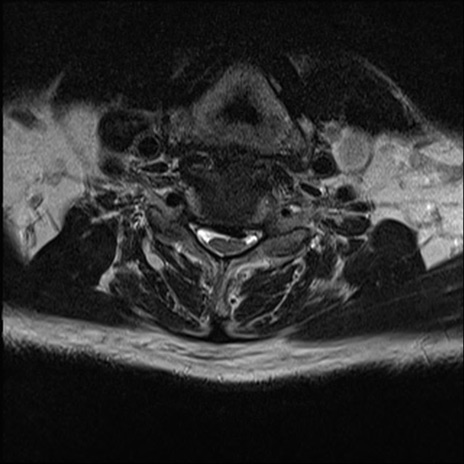

【整形】TIPS症例7 頚椎MRI T2WI(横断像)

頚椎MRI

矢状断像と横断像